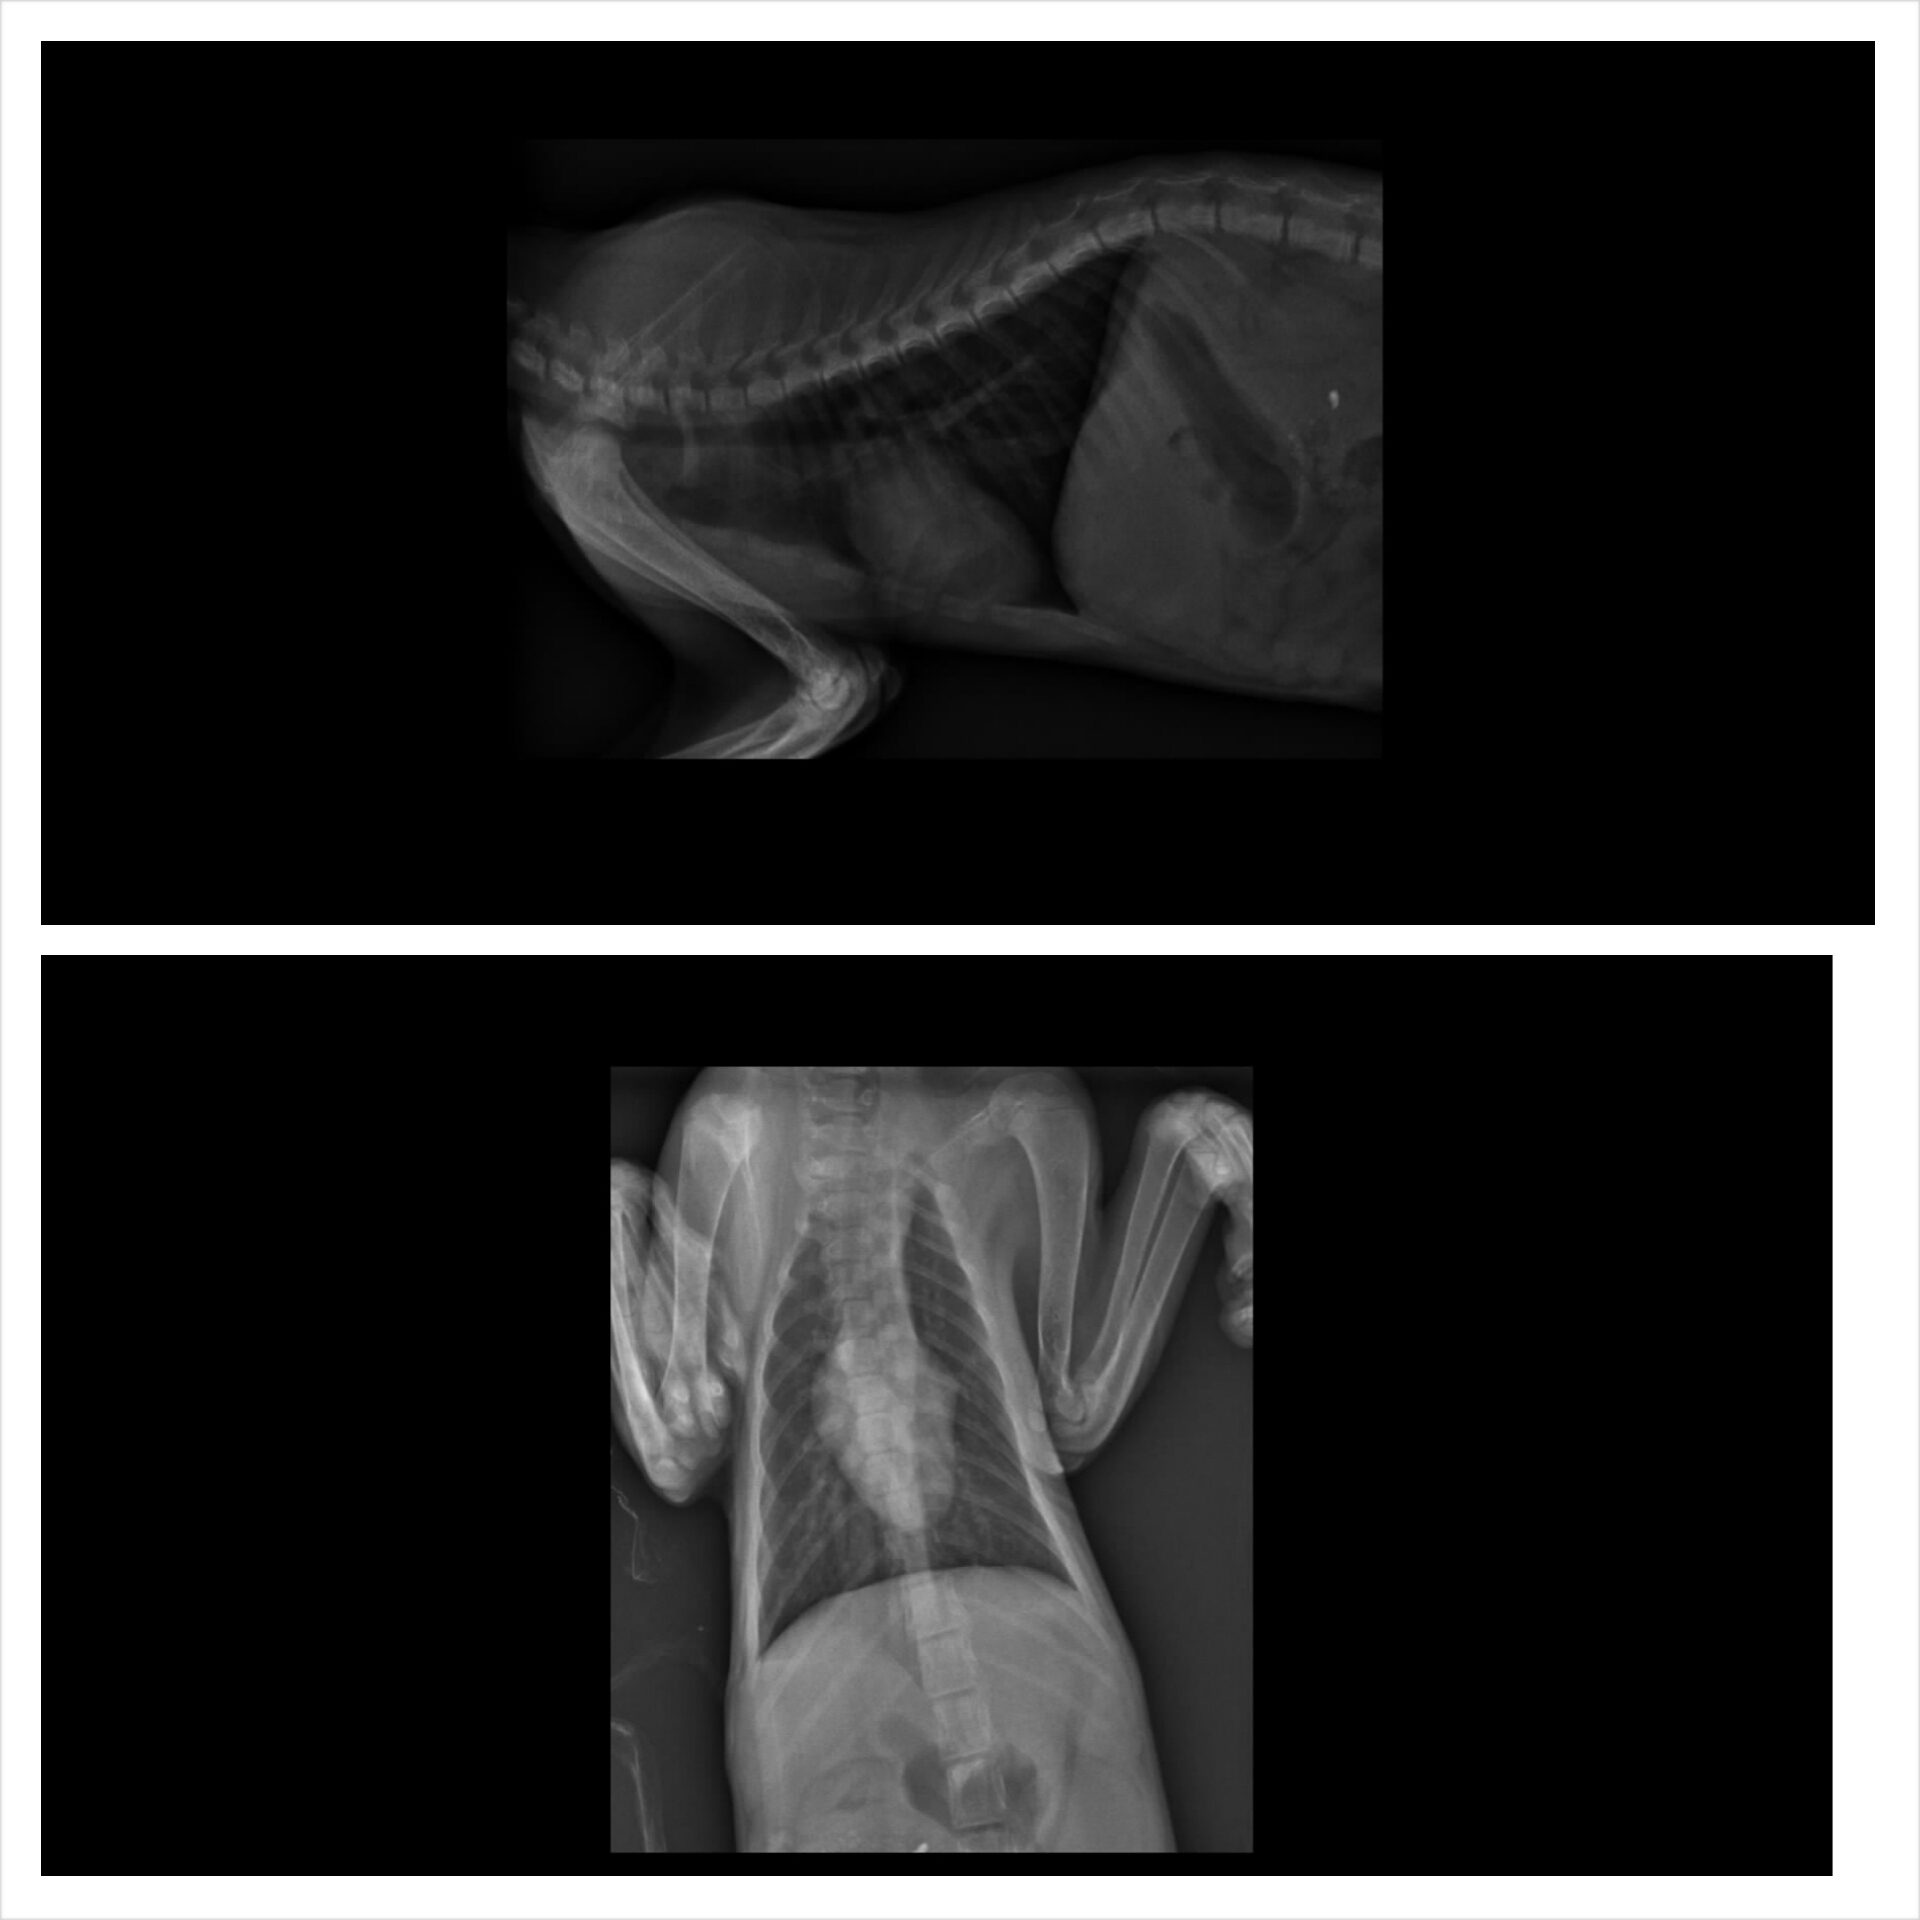

阿福檢查二合一為陰性.

照胸腔X片正常.

主要為呼吸道感染.發燒.又脫水.口腔有惡臭口炎症狀.需要輸液及噴霧治療.